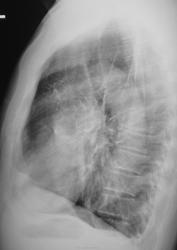

Левосторонний пневмоторакс. Ателектаз левого лёгкого.

Ребра  вроде бы целы. Пациент, насколько вижу, астеник. Булла рванула?

Булла - наиболее вероятна. Она каааааааааак рванёт!!!

Колабирование - да!, а ателектаз ли?

При пневмотораксе (тем более с таким коллабированием лёгкого) свободная жидкость в соответствующем (стороне поражения) рёберно-диафрагмальном синусе будет. Это та жидкость, что позволяет висцеральной плевре беззвучно скользить по париетальной при обычном дыхании, которая продуцируется и реабсорбируется как и другие физиологические жидкости нашего организма...wink